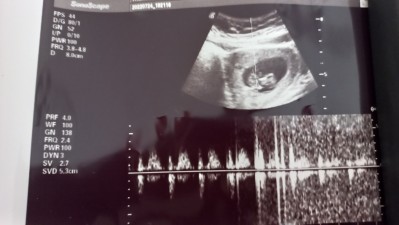

Arkadaşlar 1 dk bile bakmadı sağ olsunlar sak sak çekti verdi bunun neresi kafa neresi ayak hiç ilgilenen adam akıllı doktor yok az iyi olanlar da muanesi 300 lira ultroson fotoğrafı bakabilir misiniz neresi kafa

Gebelik haftası 10+3

Henüz belirgin olması için haftanız çok erken daha. Ama muhtemelen sol taraf kafası çünkü daha yuvarlak duruyor. Bide devlet hastanesinin çektiği ultrason görüntüleri zaten bebek seklinde pek çıkmıyor bu neresi diye kağıda bakıp duruyorsun

Canım keşke devlet olsa özeldi ama devletten beterdi sanırım dediğiniz gibi sol taraf kafası ve fotoğrafta arkası dönük sanırım

Canim bu haftada doktorlar cok bilgi vermez zaten bu haftada ayaklari kollari tam belli olmaz buyuk olan kisim kafadi bu haftalarda kafasi bedeninden buyuk olur ben 12 haftada gittim doktor daha gelisimini konusmamiz icin cok erken 1 ay sonra gel herseyi gostericem o zaman net konusicaz dedi kemikleri olusmadigi icin makinelerde zaten tam olcum yapmio yablisliklar olabiliyot bu haftalarda dedi

Canım ultrosona doğru baktığımda kafası ayaklari belliydi hareket ettiriyodu bu ultoroson kağıdında da arkası dönük o yüzden belli değil diye düşünüyorum ama beklemedi hemen çekti bıraktı uzakta bir özel doktora gitmiştim kadın 10 dk ileri geri yaptı aleti önüne dönmesini bekledi net boy ölçümü almak için uzak olmasa oraya devam edicem ama her seferinde gözüm yemiyor yakınlarda iyi bir doktor arastirmam lazım